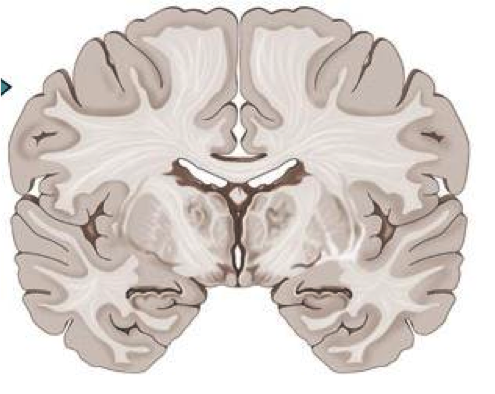

Coronal section of the brain

Description: Labelled coronal section of the brain